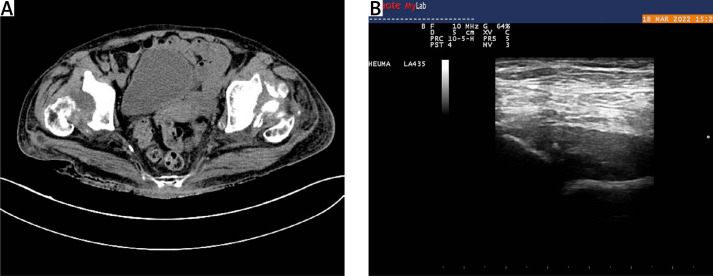

快速破坏性髋关节病(RDC)是一种罕见的髋关节炎,其特点是髋关节迅速恶化。虽然其病因尚不清楚,但已提出了几种病理生理机制。为了全面分析这一鲜为人知的疾病,我们进行了一次文献检索,重点是双侧 RDC 与类风湿性关节炎(RA)的关联。该研究提出了一个问题:长期患有类风湿性关节炎、双侧 RDC 的患者在活动能力急剧下降和髋部剧烈疼痛之前出现发热,放射学评估证实双侧髋部受到破坏。快速破坏性髋关节病,尤其是与 RA 相关时,给诊断和治疗带来了挑战。我们的综述与临床表现相印证,强调了对髋关节受累的 RA 患者保持警惕的必要性,并呼吁开展进一步研究,以了解 RDC 的机制并加强临床护理。

Rapidly destructive coxopathy (RDC) is a rare type of coxarthritis marked by swift deterioration of the hip joint. Although its cause remains unclear, several pathophysiological mechanisms are proposed. To comprehensively analyze this poorly understood condition, a literature search was conducted focusing on associations of bilateral RDC and rheumatoid arthritis (RA). The problem of long-standing RA, bilateral RDC with a febrile episode that preceded a rapid decline in mobility and severe hip pain, with radiological assessment confirmed bilateral hip destruction, was presented. Rapidly destructive coxopathy, especially when linked to RA, poses diagnostic and therapeutic challenges. Our review confirmed by the clinical picture emphasizes the need for vigilance in RA patients with hip involvement and calls for further research to understand RDC's mechanisms and enhance clinical care.